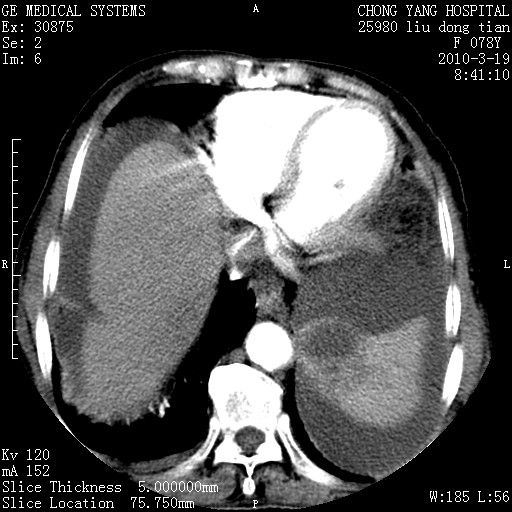

标题: CT25199:F 78Y 腹胀半年 消瘦乏力 [打印本页]

标题: CT25199:F 78Y 腹胀半年 消瘦乏力

胆囊壁增厚并明显强化,胆囊癌伴多发转移瘤可能性大,淋巴瘤不除外,右肾囊肿,胸腹水.

考虑nhl,肝、脾、腹膜腔及腹膜后多发淋巴结受侵,腹水,右肾囊肿,慢性胆囊炎,右侧少量胸腔积液。

胰头有肿块形成,胰头ca伴肝脾、腹膜腹膜后转移

胆囊有软组织影有强化,支持胆囊癌,肝脾、腹膜后淋巴结转移。

nhl的淋巴结多围绕主动脉,而且主动脉会移位,所以不考虑nhl。

分开来讲:肝左叶、尾叶病灶有不均强化像肝癌;

脾脏病灶无强化,像多发囊肿或淋巴管瘤,不除外淋巴瘤(低强化);

胆囊增生性病变:胆囊癌,腺肌增生症,慢性胆囊炎;

肝门、胰腺头、腹膜后多个团块: 淋巴瘤,转移;

腔静脉肝内段细小有无布加可能?

一元论最好了 淋巴瘤所致改变; 胆囊癌转移不像,胆囊周围肝组织清晰,肝癌淋巴结转移?三元论都不止。

胰头ca伴肝脾、腹膜腹膜后转移!

最后报的胰头癌多发转移,脾脏单独考虑囊肿或淋巴管瘤。